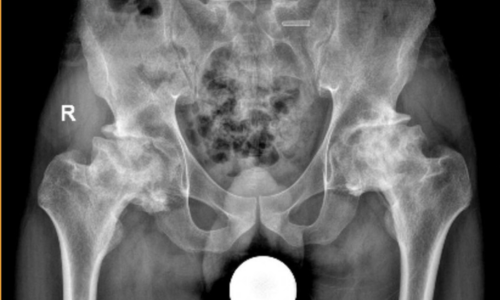

Chỉnh Hình Tâm Đức chuyên cung cấp các dịch vụ lắp ráp chân tay giả, dụng cụ chỉnh hình theo yêu cầu, cũng như tư vấn và hỗ trợ kỹ thuật sau khi lắp ráp. Công ty luôn chú trọng cập nhật công nghệ hiện đại, ứng dụng các tiến bộ kỹ thuật trong sản phẩm và dịch vụ nhằm đáp ứng tối đa nhu cầu phục hồi chức năng cho người sử dụng.